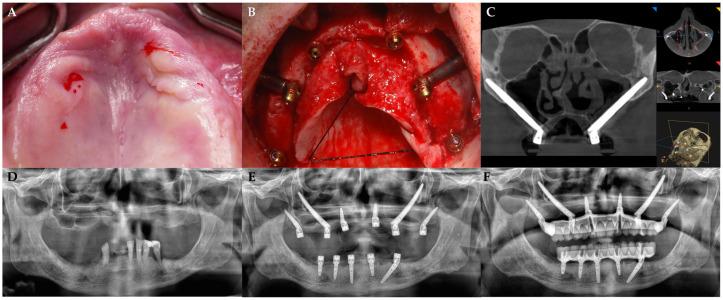

上颌全牙弓修复后患者的满意度对于评估治疗效果至关重要。这项为期一年的研究评估了患者在接受上颌全牙弓/全口即刻种植修复治疗后的满意度、生活质量和美学感知。该治疗方法结合了标准种植体、翼突种植体、经鼻窦种植体和颧骨种植体来支持固定修复体,并提供无植骨解决方案,可降低发病率和缩短治疗时间。

一项前瞻性队列研究采用便利抽样法,对接受即刻种植支持的全牙弓固定修复体治疗的严重上颌骨萎缩患者进行研究。术前及治疗后一年采用口腔健康影响程度量表(OHIP - 14)和牙科美学心理社会影响问卷(PIDAQ - 23)进行评估。根据是否存在并发症(手术、技术和机械方面)对患者进行分组,并使用Wilcoxon检验进行比较(显著性水平 = 0.05)。

共有56名患者(29名女性,27名男性)参与,未出现种植体或修复体失败情况。11名患者报告单侧鼻窦黏膜穿孔,7名患者出现技术或机械并发症。术前,根据OHIP - 14,69%的患者将其口腔状况评为不佳;治疗后这一比例显著降至21.8%(P值 < 0.0001)。一年后,PIDAQ - 23的平均得分从44.7 ± 16.6显著提高到6.8 ± 5.3(P值 < 0.0001)。有并发症和无并发症的患者之间未观察到显著差异(P值范围为0.5270至0.8920)。

采用上颌全牙弓/全口即刻种植修复治疗进行全牙弓修复,可显著改善严重上颌骨萎缩患者的美学感知和咀嚼功能。治疗后一年OHIP - 14评分显著降低,表明患者口腔健康相关不适大幅减少。临床或技术并发症并未对患者的生活质量结果或满意度产生显著影响, 这支持了该治疗方案的可靠性。